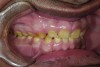

Figure 3. Preoperative 1:2 retracted right lateral view.

Figure 3

Figure 4. Preoperative 1:2 retracted left lateral view.

Figure 4